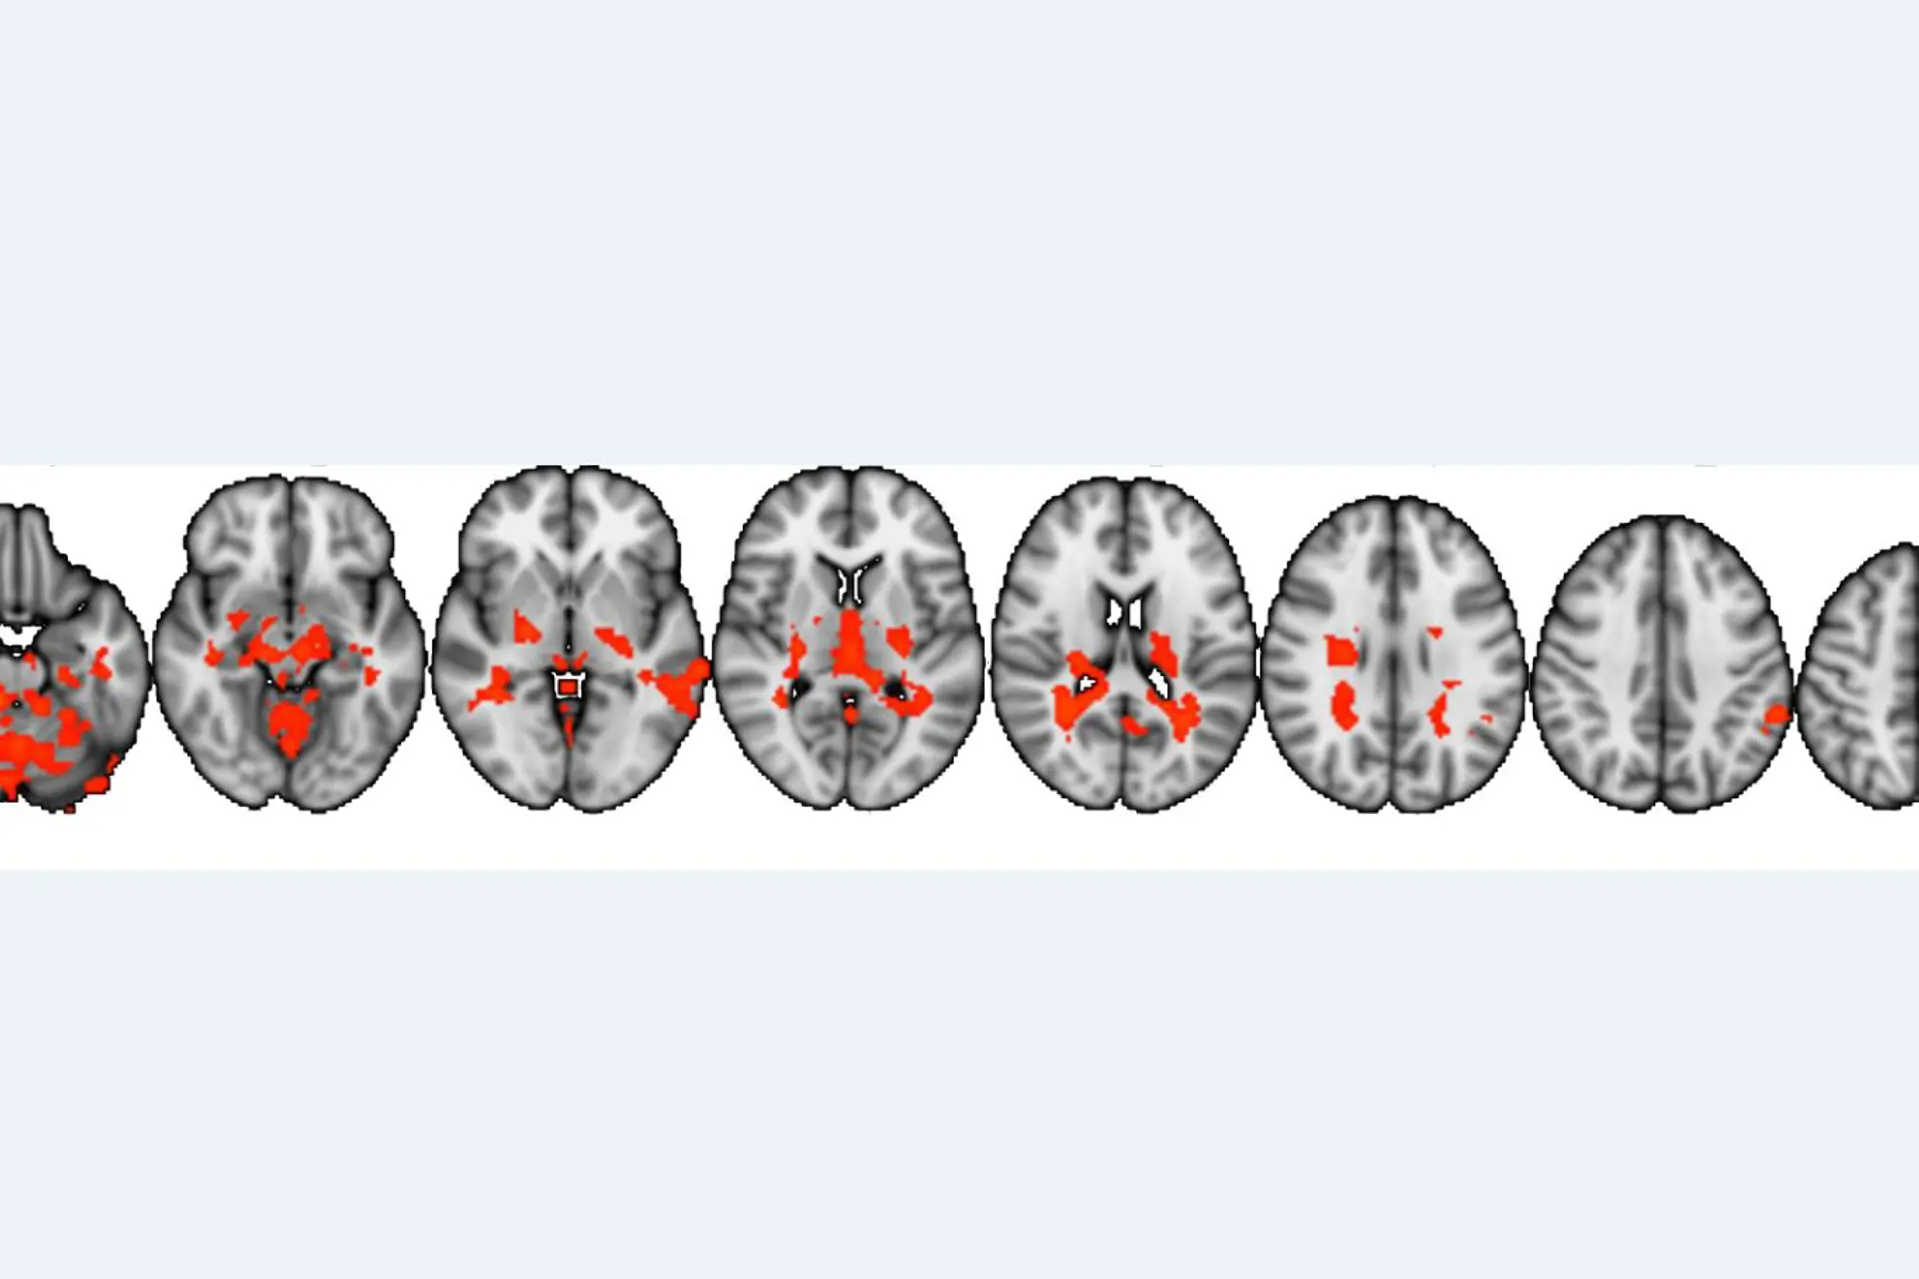

Resultatene viser at narkolepsipasientene har annerledes hjerneaktivering når de ser på filmer som de ikke syns er morsomme sammenlignet med sine slektninger. De filmene som pasientene ikke selv syns er morsomme kan allikevel være potensielt morsomme og inneholde en «morsom punchline», og kan oppfattes som morsomme av andre.

Figur fra studie: På figuren kan man se de områdene i hjernen som er mer aktive hos pasientene når de ser på filmer som de ikke selv syns er morsomme sammenlignet med slektningene deres.